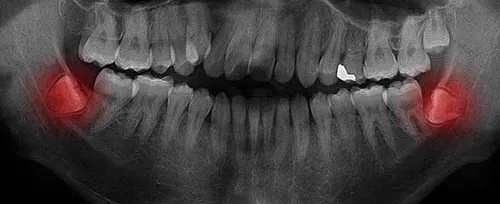

Mediante una radiografía panorámica evaluamos posición, desarrollo radicular, relación con el nervio dentario y posibles afectaciones al molar contiguo. Esto guía la planeación y reduce riesgos.

Radiografía panorámica de tercer molar